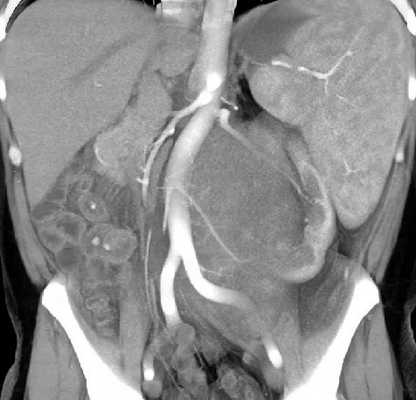

Магнитно-резонансная томография органов брюшной полости, забрюшинного пространства и позвоночника

МРТ органов брюшной полости и забрюшинного пространства ‒ это безопасный и высокоинформативный метод исследования, который позволяет не только уточнить локализацию опухоли, точные размеры новообразования и соотношение его с окружающими тканями, но и выявить метастатические очаги в печени и брюшной полости. Также МРТ дает возможность оценить состояние костных структур и мягких тканей позвоночного столба и позвоночного канала (рис. 6).

Рис. 6. МРТ нейрогенного образования забрюшинного пространства слева